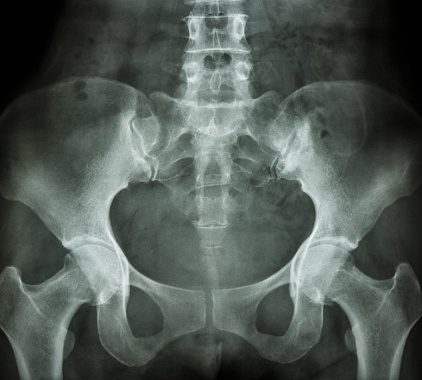

Рентген костей таза

Пройти рентгенографию костей таза стоит при наличии следующих ситуаций:

- хронические или острые боли в тазу, бедре по непонятным причинам;

- покраснение, болезненность, отечность, гематомы в области нахождения тазовых костей;

- видимое изменение осанки, формы костных структур;

- тугоподвижность в тазобедренном суставе справа или слева;

- вывих сустава;

- невозможно ходить;

- хромота;

- визуально заметное нарушение походки;

- различные травматические повреждения зоны интереса с риском переломов и трещин костей, нарушения целостности тазового кольца, ушибов;

- подтверждение артроза, артрита;

- изменение длины правой или левой нижней конечности;

- косвенные признаки инфекционно-воспалительных процессов, дефектов развития, новообразований (доброкачественных и злокачественных);

- высокая вероятность возникновения заболеваний скелета, например, остеопороза;

- обнаружение некротического поражения, вторичных или первичных метастаз;

- оценка тяжести полученной травмы, характера повреждения;

- определение объема и этапности хирургического вмешательства;

- мониторинг эффекта лечебной тактики.